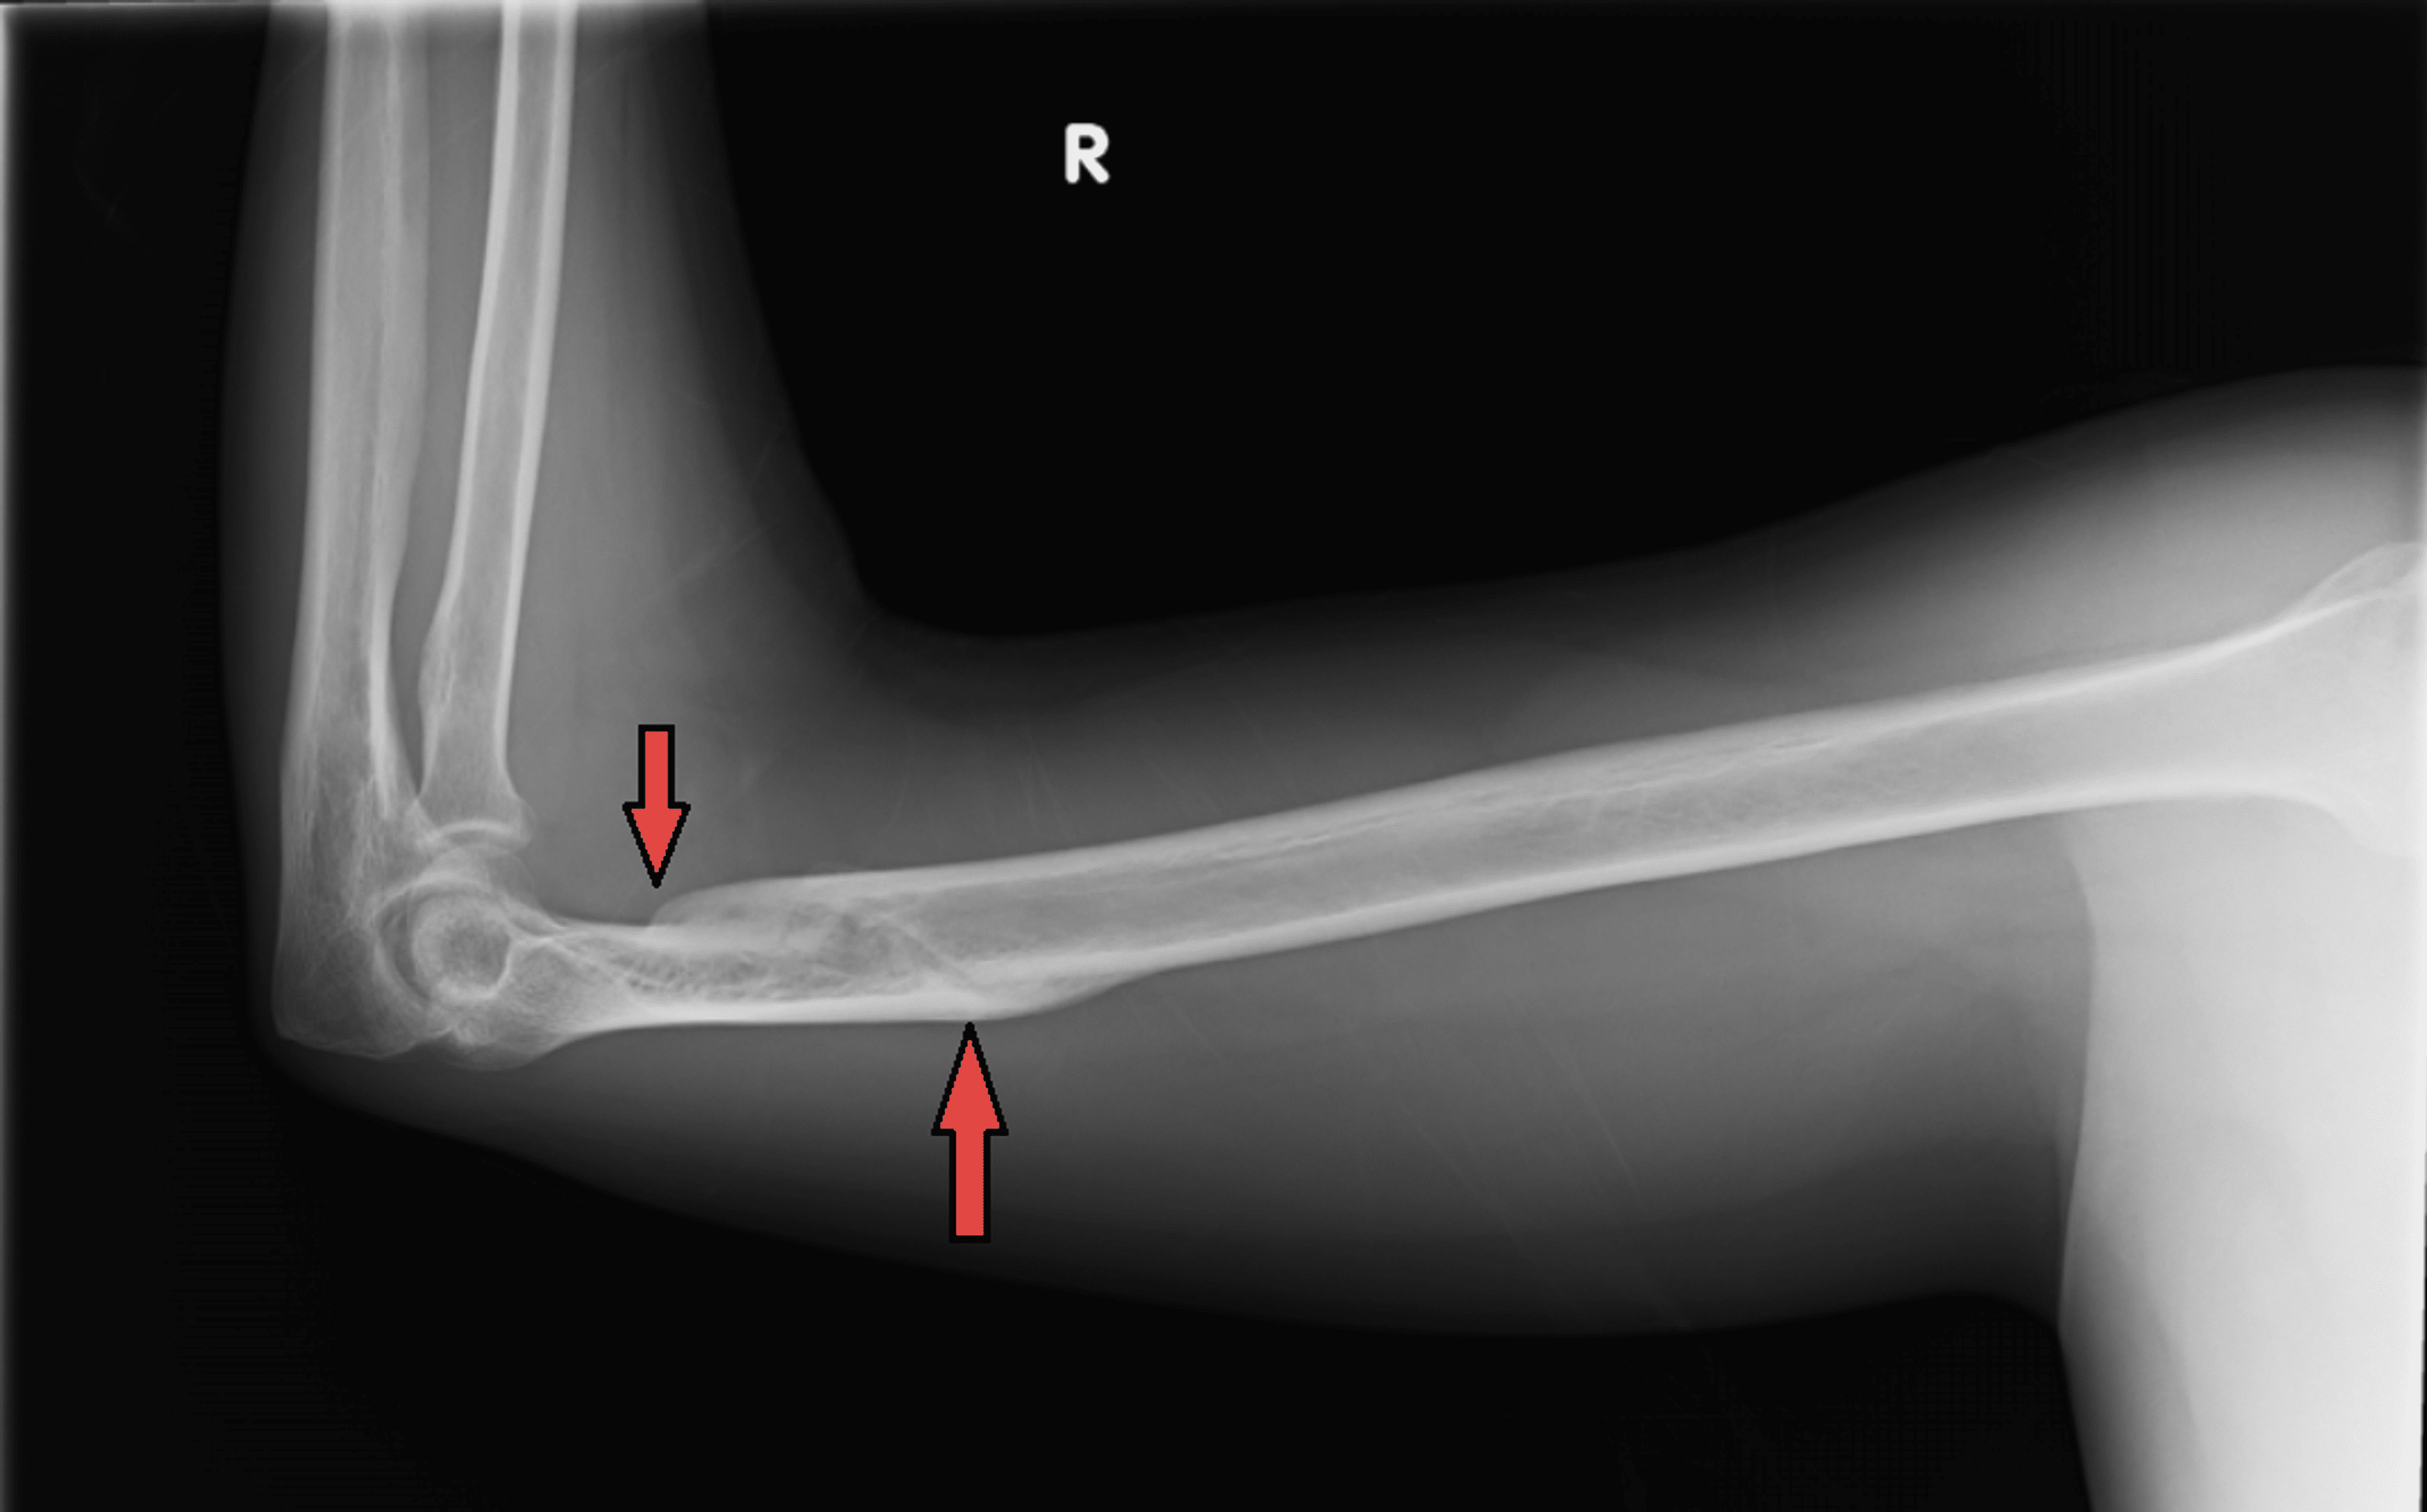

Figure 1 from Conservative Management of a Distal Humerus Spiral Spiral Fracture Humerus Arm Wrestling The humerus fails due torsional and bending stresses. The most common injury associated with arm wrestling was spiral fractures of the distal part of the humerus. Of 93 patients who presented between 2009 and. This study aimed to elucidate the current. The most common arm wrestling injury in adults is humeral shaft fracture. The dominant side is invariably affected. Humeral. Spiral Fracture Humerus Arm Wrestling.

Cureus Conservative Management of a Distal Humerus Spiral Fracture Spiral Fracture Humerus Arm Wrestling This study aimed to elucidate the current. The most common arm wrestling injury in adults is humeral shaft fracture. Torsion and bending loads cause the humerus to fail. The dominant side is invariably affected. The most common arm wrestling injury in adults is humeral shaft fracture. In this series all fractures. Spiral fractures of the distal third of the humerus. Spiral Fracture Humerus Arm Wrestling.

Cureus Conservative Management of a Distal Humerus Spiral Fracture Spiral Fracture Humerus Arm Wrestling The most common arm wrestling injury in adults is humeral shaft fracture. Torsion and bending loads cause the humerus to fail. A spiral distal humeral shaft fracture is an unusual but significant injury that can result. This study aimed to elucidate the current. Arm wrestling is an important cause of humerus shaft fracture. This study aimed to elucidate the current.. Spiral Fracture Humerus Arm Wrestling.